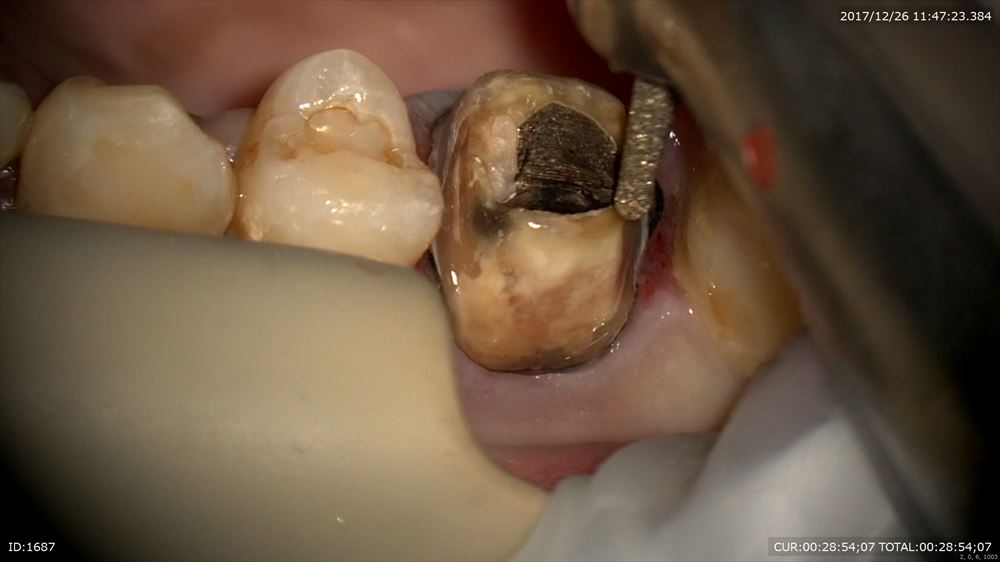

最後は精密根管治療のケース。根管が細くレントゲンでも石灰化が認められました。困った。マイクロスコープで探していきます。

ここまで拡大できました。4つ根っこがあったのです。